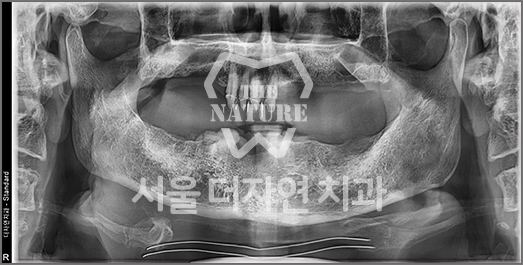

Full-Mouth Implant Restoration

Implant treatment for comprehensive full-arch restoration

This implant option is chosen to fully restore dental function. When missing teeth have been left untreated for an extended period,

the alveolar bone volume in both the maxilla and mandible is often insufficient. Therefore, a precise surgical plan must be established

with careful consideration of each patient's overall health condition.

• BEFORE: 2022.12.15

• AFTER: 2023.02.23